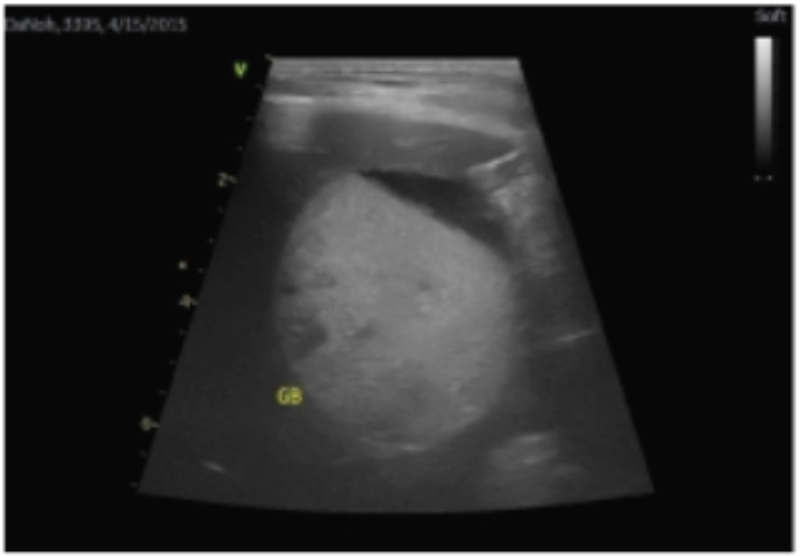

보호자분이 본원에 내원하기 직전 병원에서 검사했던 초음파 검사 사진을 봤을 때 굉장히 팽창되어 있다는 게 눈에 띄었습니다.

본원에서 다시 평가를 했을 때에도 담낭을 메우고 있는 물질의 양상은 Type 2에 해당하는 비교적 초기 상태이긴 하지만 담낭이 굉장히 팽만된 상태였고, 이런 흐름이 지속되어 간다면 주변으로 염증을 유발하여 간에도 더 큰 영향을 줄 수 있고 기력 저하, 식욕 부진의 증상이 나타날 수 있는 상태였습니다.

(내원 직전 병원에서 검사한 초음파 사진 ▲)